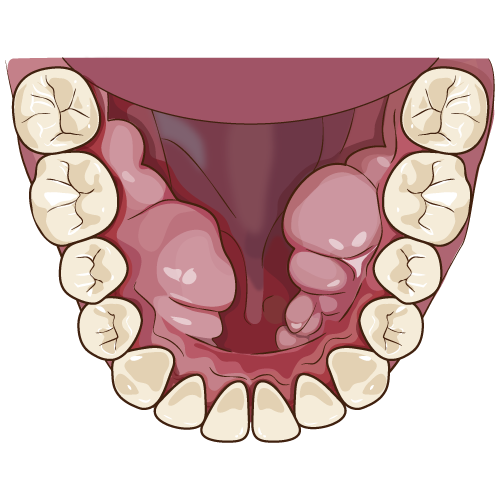

写真 左から 口内炎 手足口病 ヘルパンギーナ

水泡を伴うものには、ウイルス感染によるものと自己免疫疾患によるものがあります

③ヘルパンギーナ:コクサッキ―Aウイルス感染により幼児に好発し発熱や口峡部の左右対称の水泡を形成し疼痛を伴う

④手足口病:コクサッキーウイルスA16またはエンテロウイルスによる感染により、1~4歳に好発し発熱を初発症状とし

両手、両足、口腔に水泡を形成し5~7日で治癒します

①天疱瘡(てんぽうそう):中年女性に好発し口腔内に水泡を形成する。水泡は破れてびらんとなり、難治性である

②類天疱瘡(るいてんぽうそう):水泡形成後、破れて潰瘍をつくるが全身症状は軽く、予後も良好である